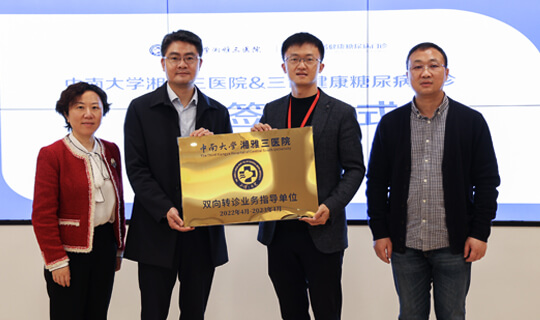

三甲医院双向转诊